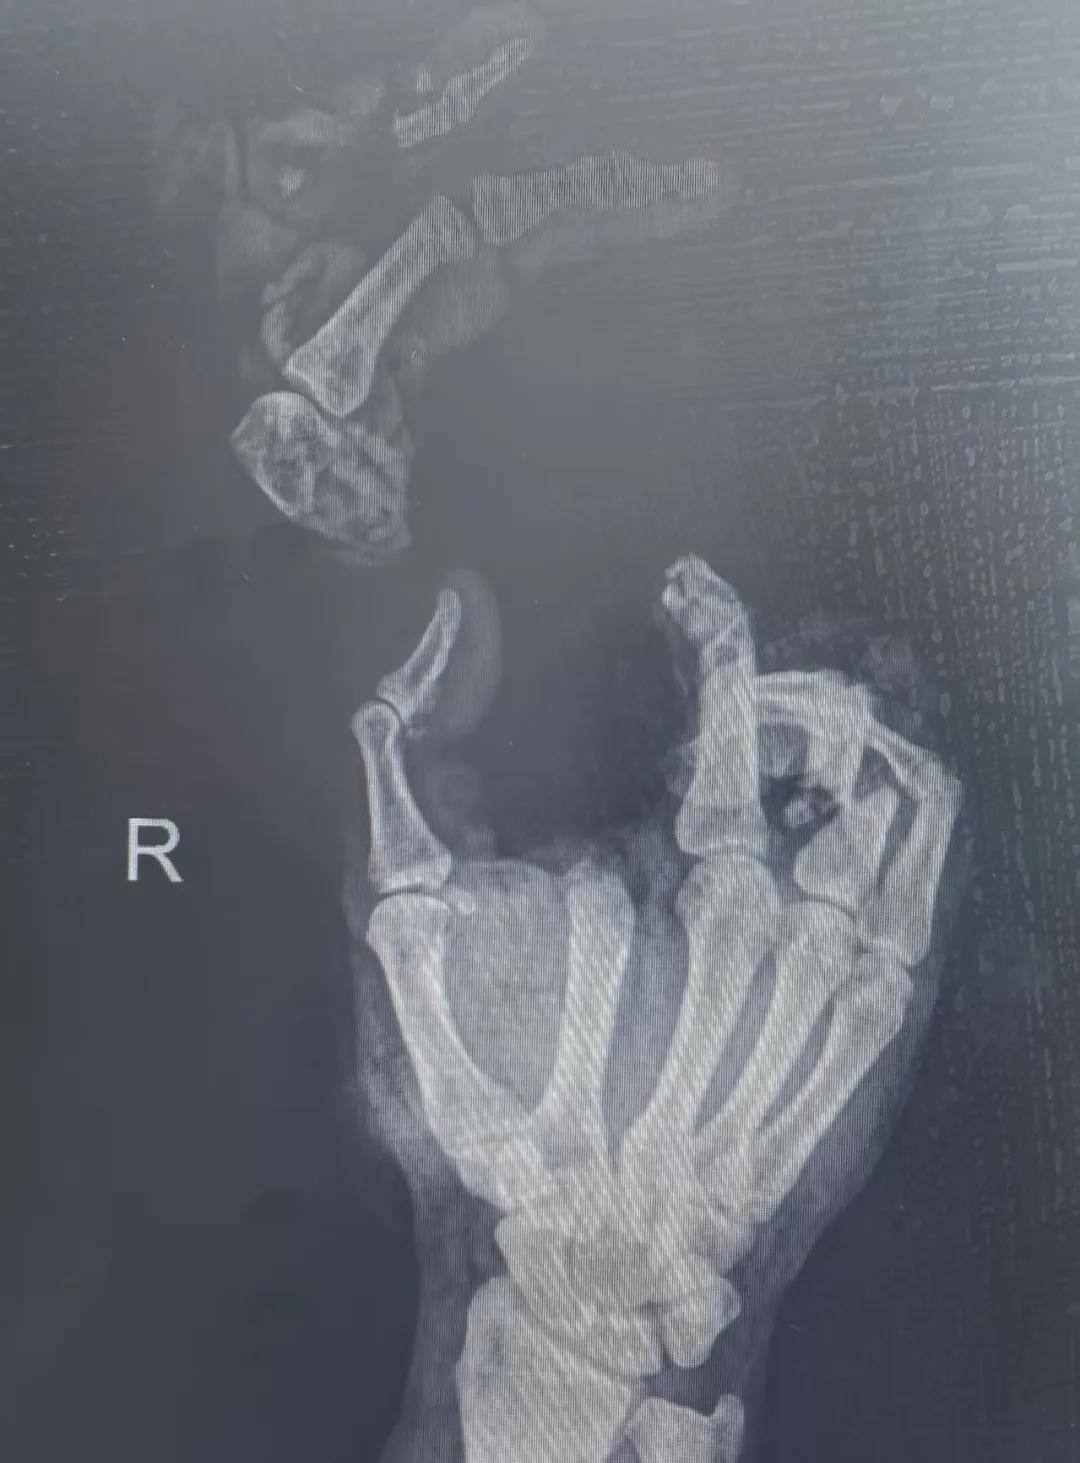

5月20日,市二院顯微外科燒傷整形科收治了3例因麥?zhǔn)毡晦r(nóng)機(jī)“咬傷”、農(nóng)具劃傷的患者。其中,56歲的劉某在收麥子時(shí)被打谷機(jī)皮帶絞傷右手,致手掌、食指、中指、環(huán)指嚴(yán)重毀損傷,骨、關(guān)節(jié)外露,因當(dāng)?shù)蒯t(yī)院無法治療,被家人緊急送往市二院顯微手足燒傷整形外科救治。“當(dāng)時(shí)整個(gè)右手血肉模糊,看上去都是爛的,我以為這個(gè)手是肯定保不住了。”患者家屬回憶當(dāng)時(shí)的場(chǎng)景仍然膽戰(zhàn)心驚。

患者入院后,經(jīng)X線檢查及創(chuàng)面檢查,醫(yī)生診斷為右手食指、中指及環(huán)指旋轉(zhuǎn)撕脫性離斷。接診的顯微手足燒傷整形外科醫(yī)護(hù)人員立即完善了各項(xiàng)術(shù)前準(zhǔn)備,并安排急診手術(shù)。因創(chuàng)面污染嚴(yán)重以及離斷肢體損傷程度較重,手術(shù)歷時(shí)近10小時(shí)。在沈衛(wèi)軍主任的帶領(lǐng)下,科室團(tuán)隊(duì)成功為其進(jìn)行了創(chuàng)面擴(kuò)創(chuàng)、斷肢再植術(shù),術(shù)后患指血運(yùn)良好,在進(jìn)一步觀察治療中。